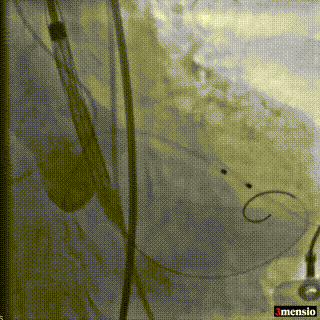

根部造影,可见明显反流,猪尾在右窦

调整猪尾到无窦,输送器跨瓣,确认位置

起搏状态下释放,造影观察瓣膜位置

第一次释放下滑,重新回收定位